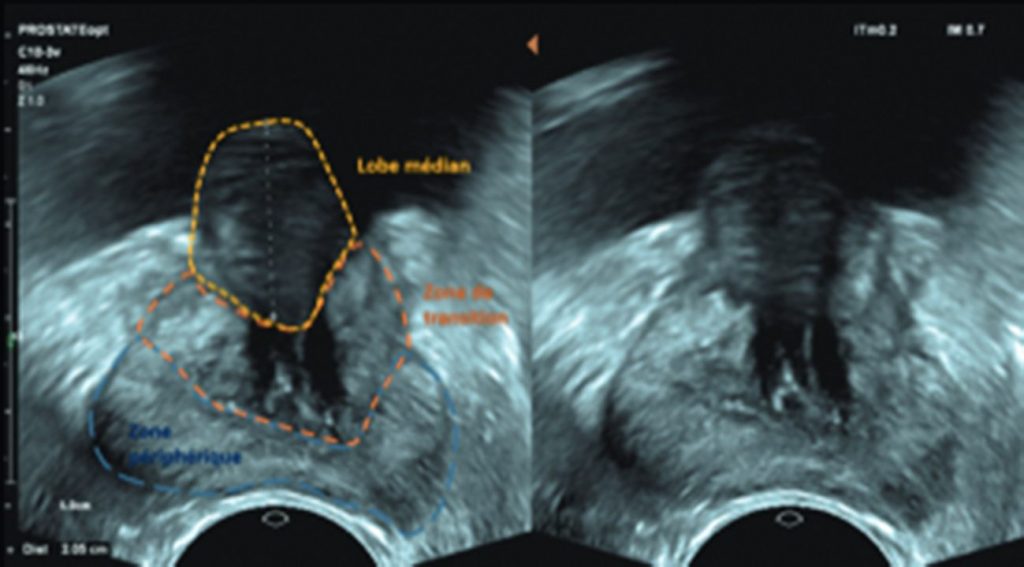

L’échographie endorectale (figure 25.3) permet une meilleure visualisation de la prostate. Elle est recommandée dans certaines situations particulières :

- mauvaise estimation du volume prostatique, au TR et en échographie sus-pubienne ;

- avant traitement chirurgical.

Fig. 25.3. Échographie prostatique par voie endorectale ; plan axial.

La voie endorectale fournit une meilleure visaulisation de la zone périphérique, de la zone de transition et du lobe médian.

Source : CERF, CNEBMN, 2022.

Elle utilise une sonde endocavitaire.